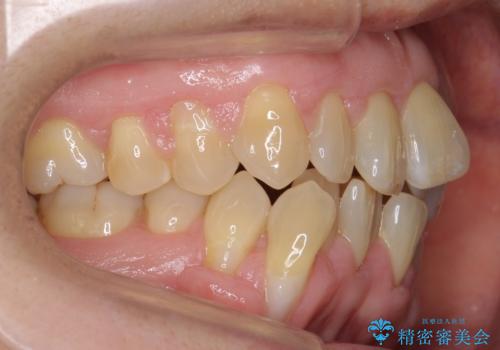

- 前歯のがたつきを主訴に来院。

右下の犬歯が歯ぐきが痩せて、歯肉退縮しておりそれを抜歯しました。

上の前歯はIPRを行なっています。

右下の犬歯の1本抜歯で最小限の抜歯で並べることができました。

奥歯も上下交互になるようにかみ合わせることができました。